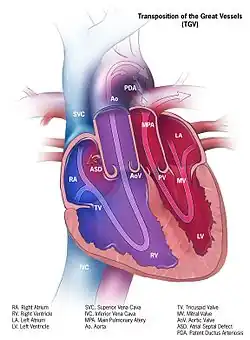

| Illustration of transposition of the great vessels | |

Transposition of the great vessels (TGV) is a group of congenital heart defects involving an abnormal spatial arrangement of any of the great vessels: superior and/or inferior venae cavae, pulmonary artery, pulmonary veins, and aorta. Congenital heart diseases involving only the primary arteries (pulmonary artery and aorta) belong to a sub-group called transposition of the great arteries (TGA), which is considered the most common congenital heart lesion that presents in neonates.[2]

Dextro-Transposition of the great arteries (also known as dextro-TGA) is a cyanotic heart defect in which the aorta arises from the right ventricle and the pulmonary artery arises from the left ventricle. This switch causes deoxygenated blood from the right heart to be pumped immediately through the aorta and circulated throughout the body and the heart itself, bypassing the lungs altogether. In this same condition, the left heart continuously pumps oxygenated blood back into the lungs through the pulmonary artery, instead of out into the body's circulation as it normally would. In effect, two separate "parallel" circulatory systems are created. It is called a cyanotic congenital heart defect (CHD) because the newborn infant turns blue (cyanotic) from the lack of oxygen.

In many cases, TGV is accompanied by other heart defects, the most common type being intracardiac shunts such as atrial septal defect including patent foramen ovale, ventricular septal defect, and patent ductus arteriosus. Stenosis, or other defects, of valves and/or vessels may also be present.